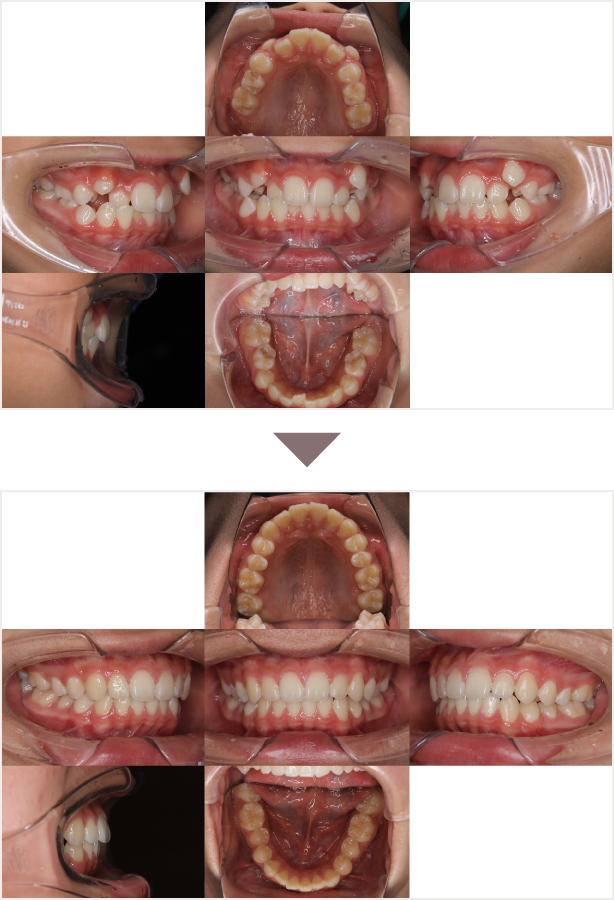

症例叢生

性別

期間7年7ヶ月

治療内容N-Bimler装置、Neo-Capを使用して治療

治療における

副作用・リスク

装着しないと効果は出ません

金額ビムラー装置:550,000円

ネオキャップ:4本

合計:572,000円